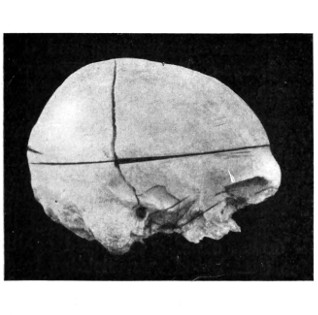

42. A comminuted fracture of the skull 112

43 A and B. An explosive fracture of the vault of the skull 113